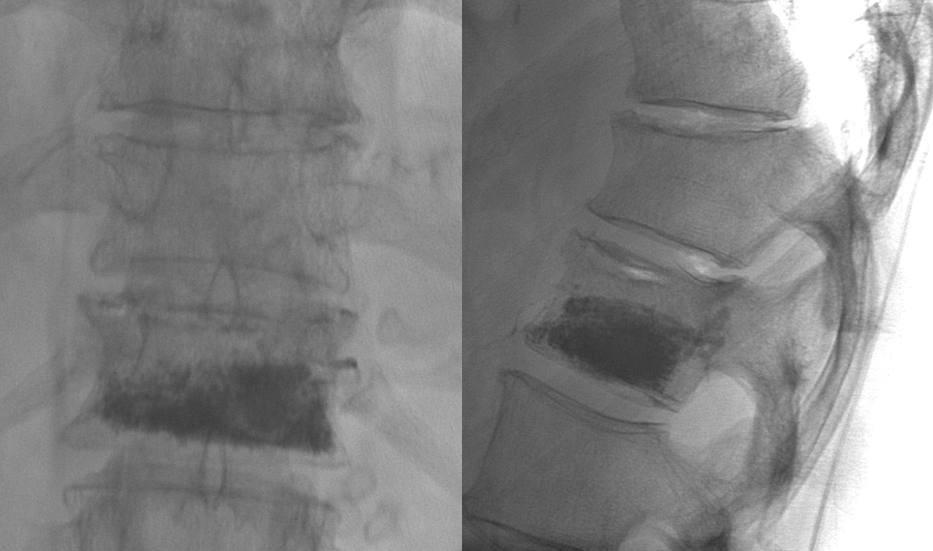

Kyphoplasty

Treatment with bone cement results in prompt relief of pain from vertebral compression fractures.

Balloon kyphoplasty is an outpatient procedure using sedation.  Dr. Burke will do a comprehensive exam and review of x-ray and MRI images to determine if you are a candidate for this procedure.